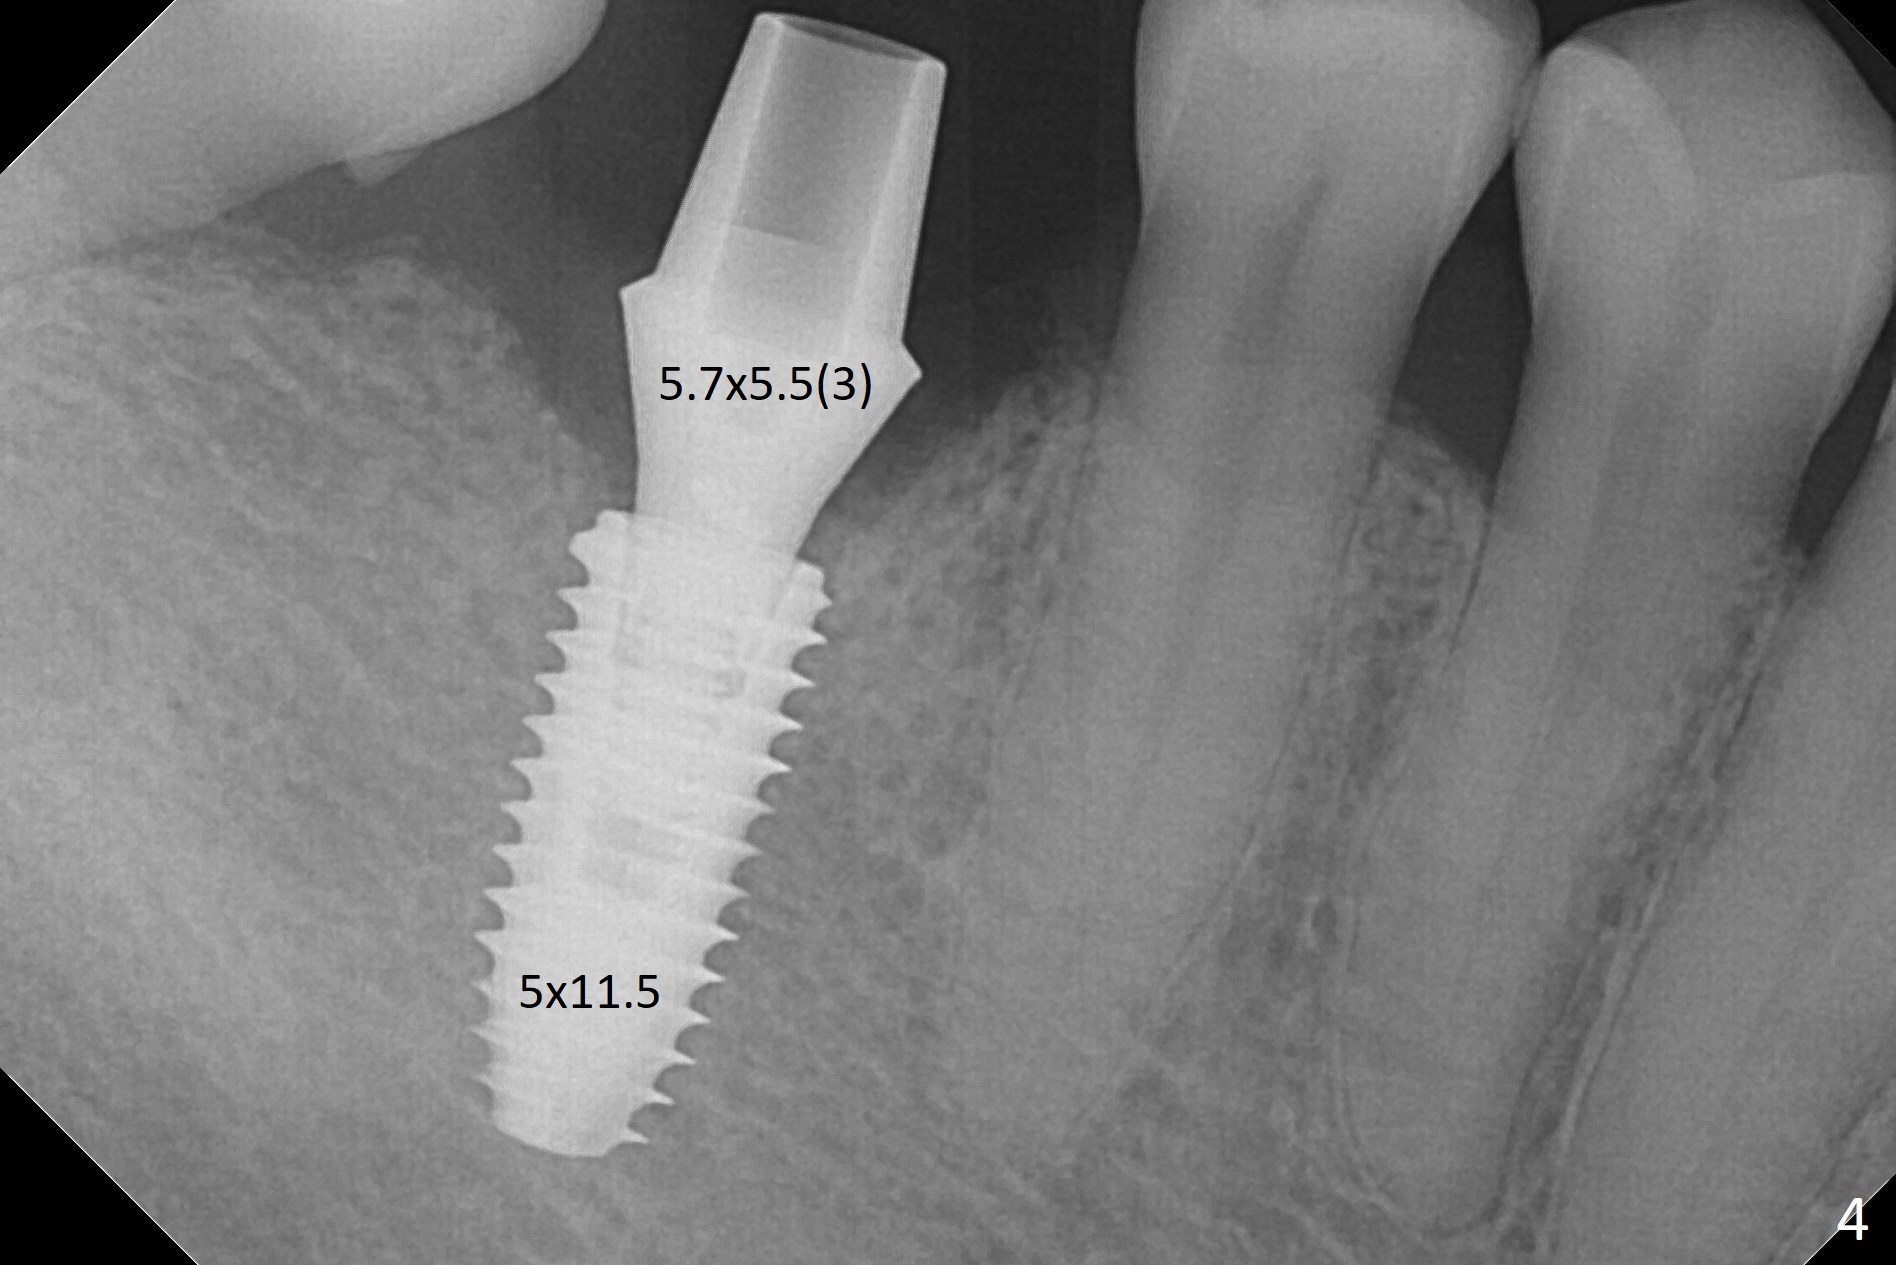

When the residual roots of the tooth #30 (Fig.1) are removed, the buccal crest is found ~ 2 mm apical to the lingual one (Fig.2 <); while the initial depth of osteotomy is 11.5 mm (yellow lines), the parallel pin is 10 mm long.  To place a 5x11.5 mm implant at the level of the buccal crest (Fig.4 (>45 Ncm)), subsequent osteotomy depth is 13 mm using the lingual crest as a landmark (Fig.3 (4 mm drill in place)).  After insertion of a 5.7x5.5(3) mm abutment, Vanilla Graft is placed (Fig.5 * with 2 mm buccal gap).  The abutment with a provisional is loose 4 months postop (Fig.6).   The permanent restoration is cemented 6 months postop.  The abutment screw is loose and fractured 8 and 11 months post cementation, respectively (Fig.7).  The fractured screw seems to be loose within the implant well and is easily re-winded out using Screw Removal Kit (sr-kit.html).  When the crown/abutment at #30 is loose 2nd time 1 year 7 months post cementation (Fig.8 taken post retightening), the screw at #19 fractures.  The tooth #2 needs a crown.  The patient cannot use the anterior teeth, since the teeth #8 and 9 have root fracture.  Can extraction and bone graft increase bone height?  The screw re-fractures 9 months later (Fig.9).  The dislodged crown is sectioned; the abutment is reseated completely (Fig.10) for a new crown. The tooth #2 needs RCT, B-U and crown, while the tooth #1 extraction (Fig.11).